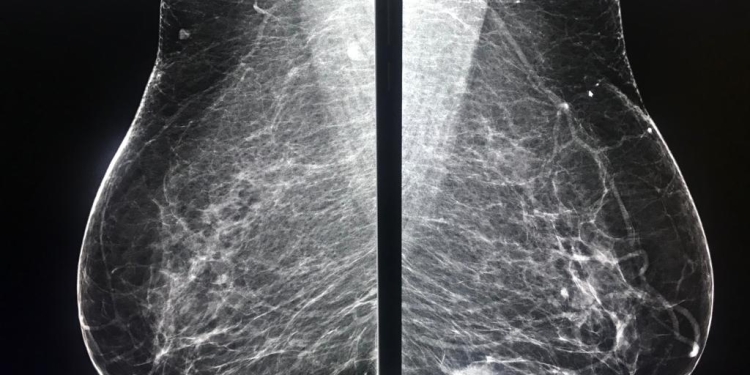

Medicul timișorean a explicat faptul că mamografia reprezintă o radiografie a sânilor, utilizată atât pentru screening, cât și pentru diagnostic.

„Avantajul suprem al mamografiei îl reprezintă identificarea microcalcificărilor de la nivelul sânului, care pot fi un semnal de alarmă în apariția cancerului mamar chiar și înainte cu doi ani. (…) De reținut! Este o metodă iradiantă de examinare a sânului, care folosește însă doze foarte mici de radiații în scop de diagnostic. Uneori, examenul mamografic inițial trebuie continuat cu alte metode imagistice complementare: ecografie/biopsie mamară. Rezultatele examinării mamografice trebuie să fie în acord cu standardele internaționale. Acestea se vor comunica pacientei, împreună cu concluziile și eventualele recomandări”, a precizat Diana Manolescu.